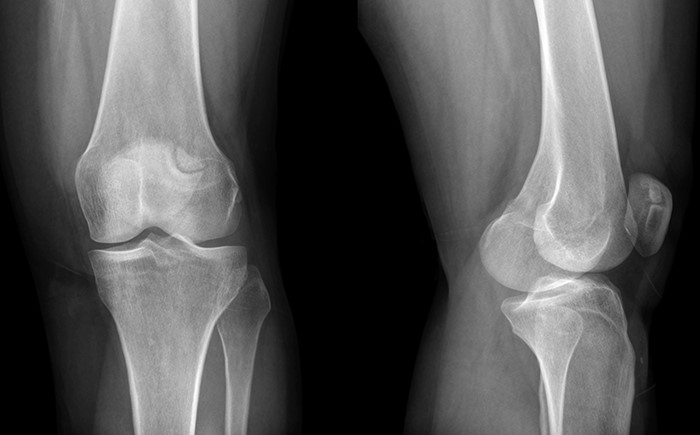

Рентгенологическое исследование коленного сустава

Рентгенологическое исследование коленного сустава — важный инструмент для диагностики травм, повреждений и болей, связанных с изменениями в костной ткани, сухожилиях и хрящах.

При первичной диагностике чаще всего используются результаты, полученные в двух взаимно перпендикулярных проекциях: прямой и боковой.

Снимки в прямой проекции обычно делают сзади, когда пациент лежит на животе. Если состояние больного тяжелое, рентген может быть выполнен в положении на спине, при этом укладка должна быть максимально близка к стандартной.

Рентген в боковой проекции выполняется, когда пациент лежит на боку. Если повреждено левое колено, пациента укладывают на этот бок, поврежденное колено слегка сгибается и располагается наружной поверхностью на столе. Правая нога сгибается в коленном и тазобедренном суставах и может быть отведена назад или прижата к животу.

На рентгеновском снимке здорового колена костная структура выглядит однородной и целостной. Суставная щель имеет равномерную и достаточную ширину, отсутствуют смещения и деформации, а строение сустава симметрично. Также не наблюдаются опухоли или другие уплотнения тканей.

Если у пациента повреждены связки или сухожилия, на рентгеновском изображении межсуставная щель будет увеличена. При наличии артрита наблюдается истончение ближайших костных пластинок и увеличение щели. В некоторых случаях толщина хрящевой прослойки может уменьшаться, а кости — увеличиваться и деформироваться по краям, что свидетельствует о наличии артроза. Сужение межсуставной щели также может указывать на повреждение мениска.

На рентгенограмме хорошо видны изменения в костной ткани, проявляющиеся в уменьшении числа костных перекладин, их истончении, искривлении и частичном или полном рассасывании из-за остеопороза. Кость теряет кальций, становится более прозрачной на снимке, а ее края уплотняются и становятся четче.